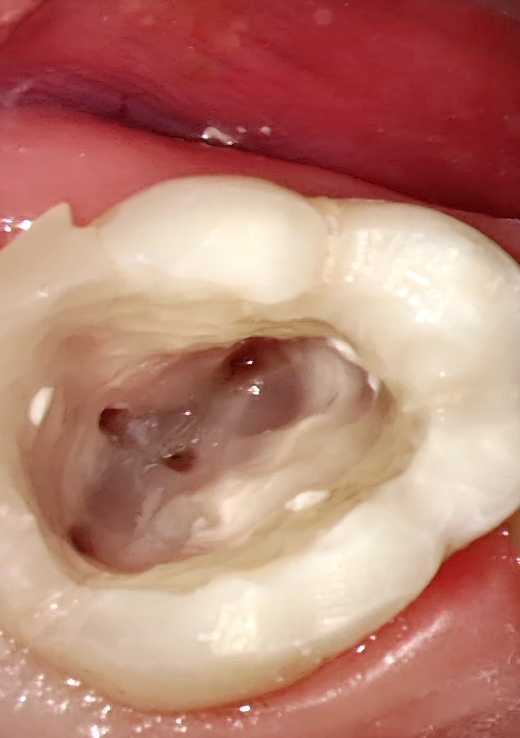

A fogak gyökérkezelését jellemzően akkor végezzük, ha a fogszuvasodás a zománcot és a dentint, azaz a kemény fogállományt is elpusztítva eljutott a fogbélig és ott gyulladást idézett elő.

Pre-endodontális restauráció

Gyökérkezelés első fázisa

Megnyitás,erek idegek eltávolítása